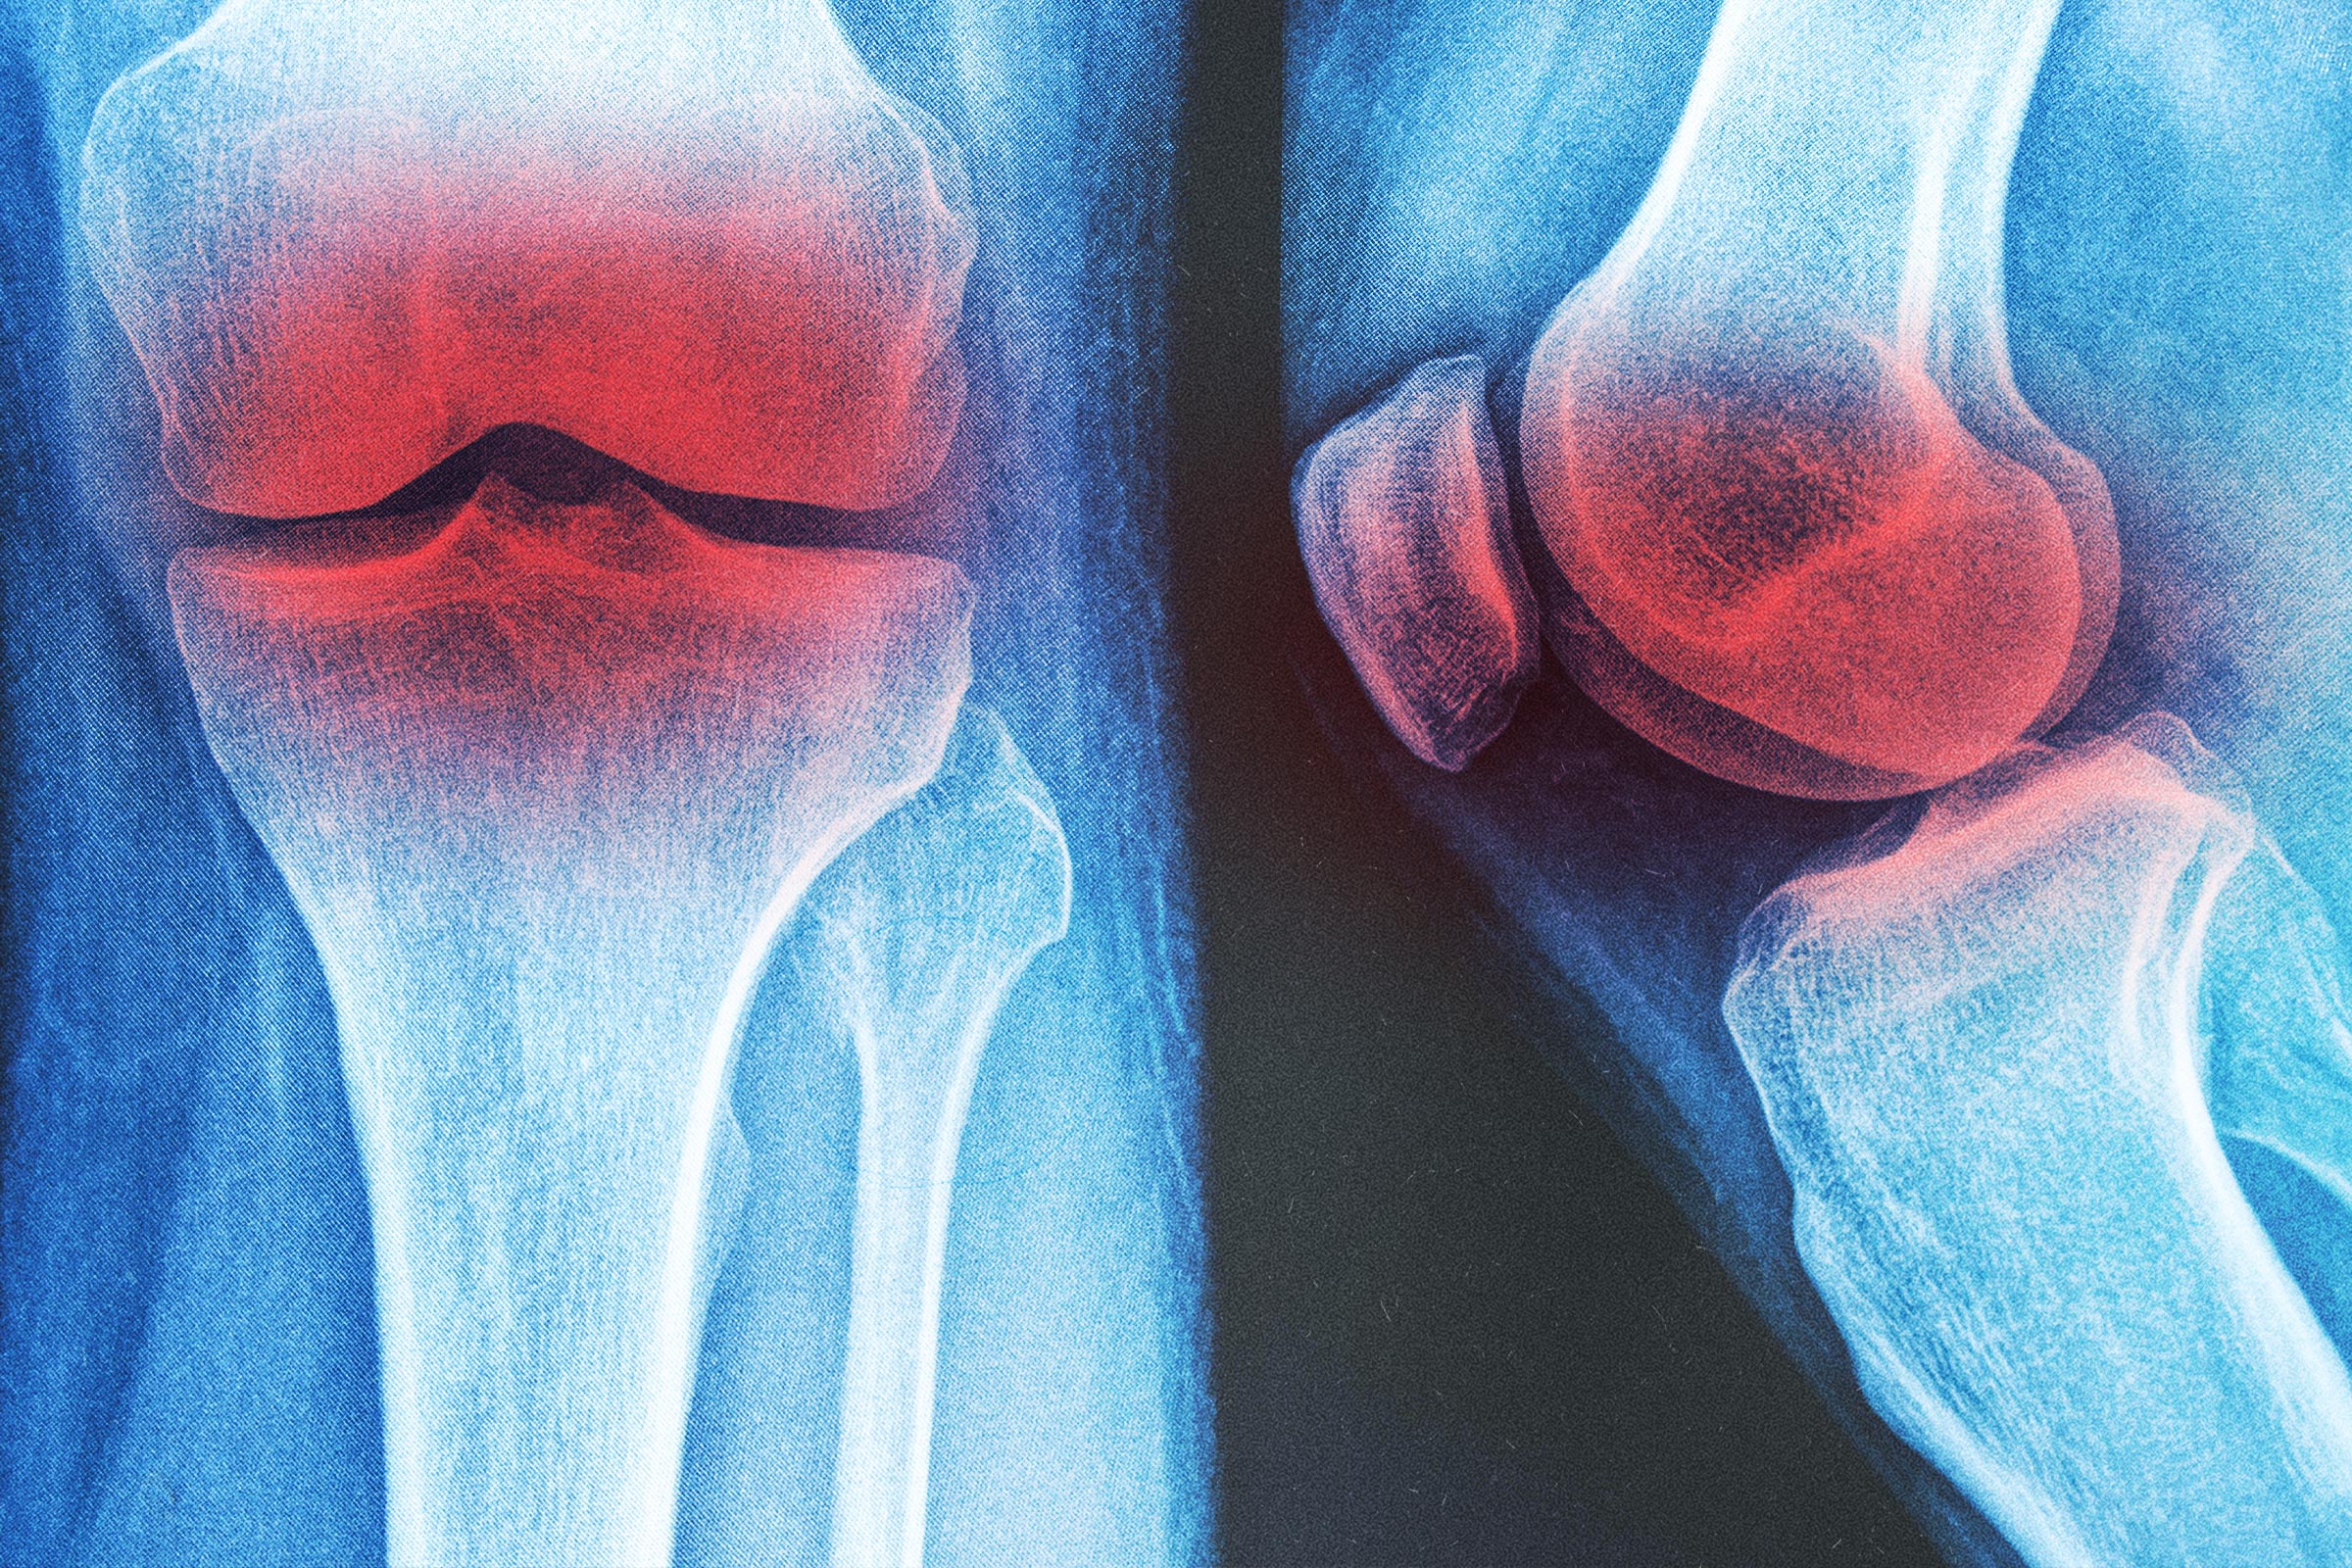

Approximately 10 percent of men and 13 percent of women older than 60 have knee arthritis, a condition associated with pain and disability.

Nonsteroidal anti-inflammatory drugs, such as ibuprofen, are commonly prescribed treatments but have side effects. According to research, adverse effects include a fourfold increased risk of gastrointestinal bleeding and more than double the risk of acute kidney injury within 30 days in patients older than 65.

A network meta-analysis, published in June in PLOS One, compared 12 physical therapy interventions for knee arthritis. Researchers found that of the 12, knee braces were the best choice. Following that, hydrotherapy and general exercise were deemed the most effective.

According to the meta-analysis findings, knee bracing showed the highest likelihood of being the best intervention, as it produced high scores in reducing pain, relieving stiffness, and improving function. Hydrotherapy was very effective in alleviating pain, while general exercise was consistently effective in alleviating pain and boosting function. Shockwave therapy and high-intensity laser therapy had some benefits, and ultrasound had the lowest effectiveness scores.